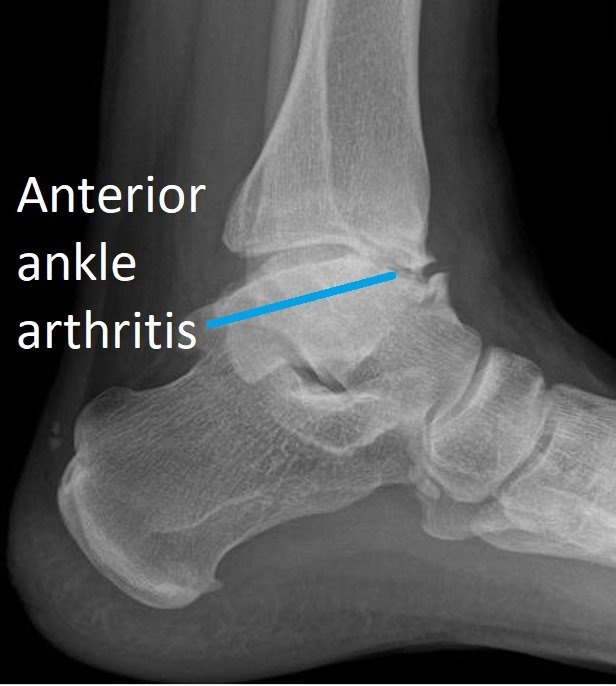

From www.sportsmedreview.com